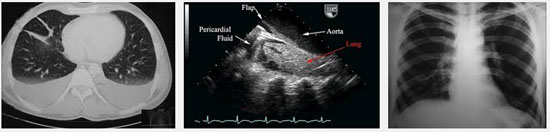

CTMTP: Bạch cầu tăng 13.000/mm3, bạch cầu ái toan chiếm ưu thế 11%, bạch cầu đa nhân trung tính 70%; chỉ số CRP: 47 mg/L (bình thường < 3); men gan AST: 88 U/L, ALT: 100 U/L, GGT: 100 U/L; men tim CK-MB, Troponin T: Âm tính; X-quang phôi: bóng tim lớn nhẹ, tràn dịch màng phổi phía bên (T); siêu âm tim: màng ngoài tim Echo kém, dày 3 - 5 mm; siêu âm bụng: Gan lách bình thường, ghi nhận TDMP (T), bề dày lớp dịch 37 mm.

Sau 3 ngày điều trị bệnh nhân vẫn còn sốt, đau ngực tăng, đau cả ngực (P) và (T). X-quang phổi kiểm tra cho thấy TDMP bên (T) tăng. Siêu âm màng phôi cho hình ảnh TDMP 2 bên. Bệnh nhân được chọc dịch màng phổi để xét nghiệm, kết quả như sau:

-X-quang phổi, siêu âm không còn dịch màng phổi.

Ngày 01/7/2014 | Ngày 08/7/2014 | Ngày 25/7/2014 |